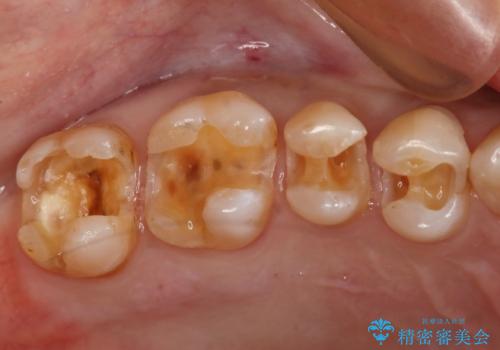

- かなり昔に入れた銀歯の部分のチェックをご希望でご来院されました。

上下ともに銀歯が多く入っており、その下に虫歯が疑われる状態でした。

詰め物の大きさや虫歯の状態から個々に材料と治療範囲を決定し治療に入りました。